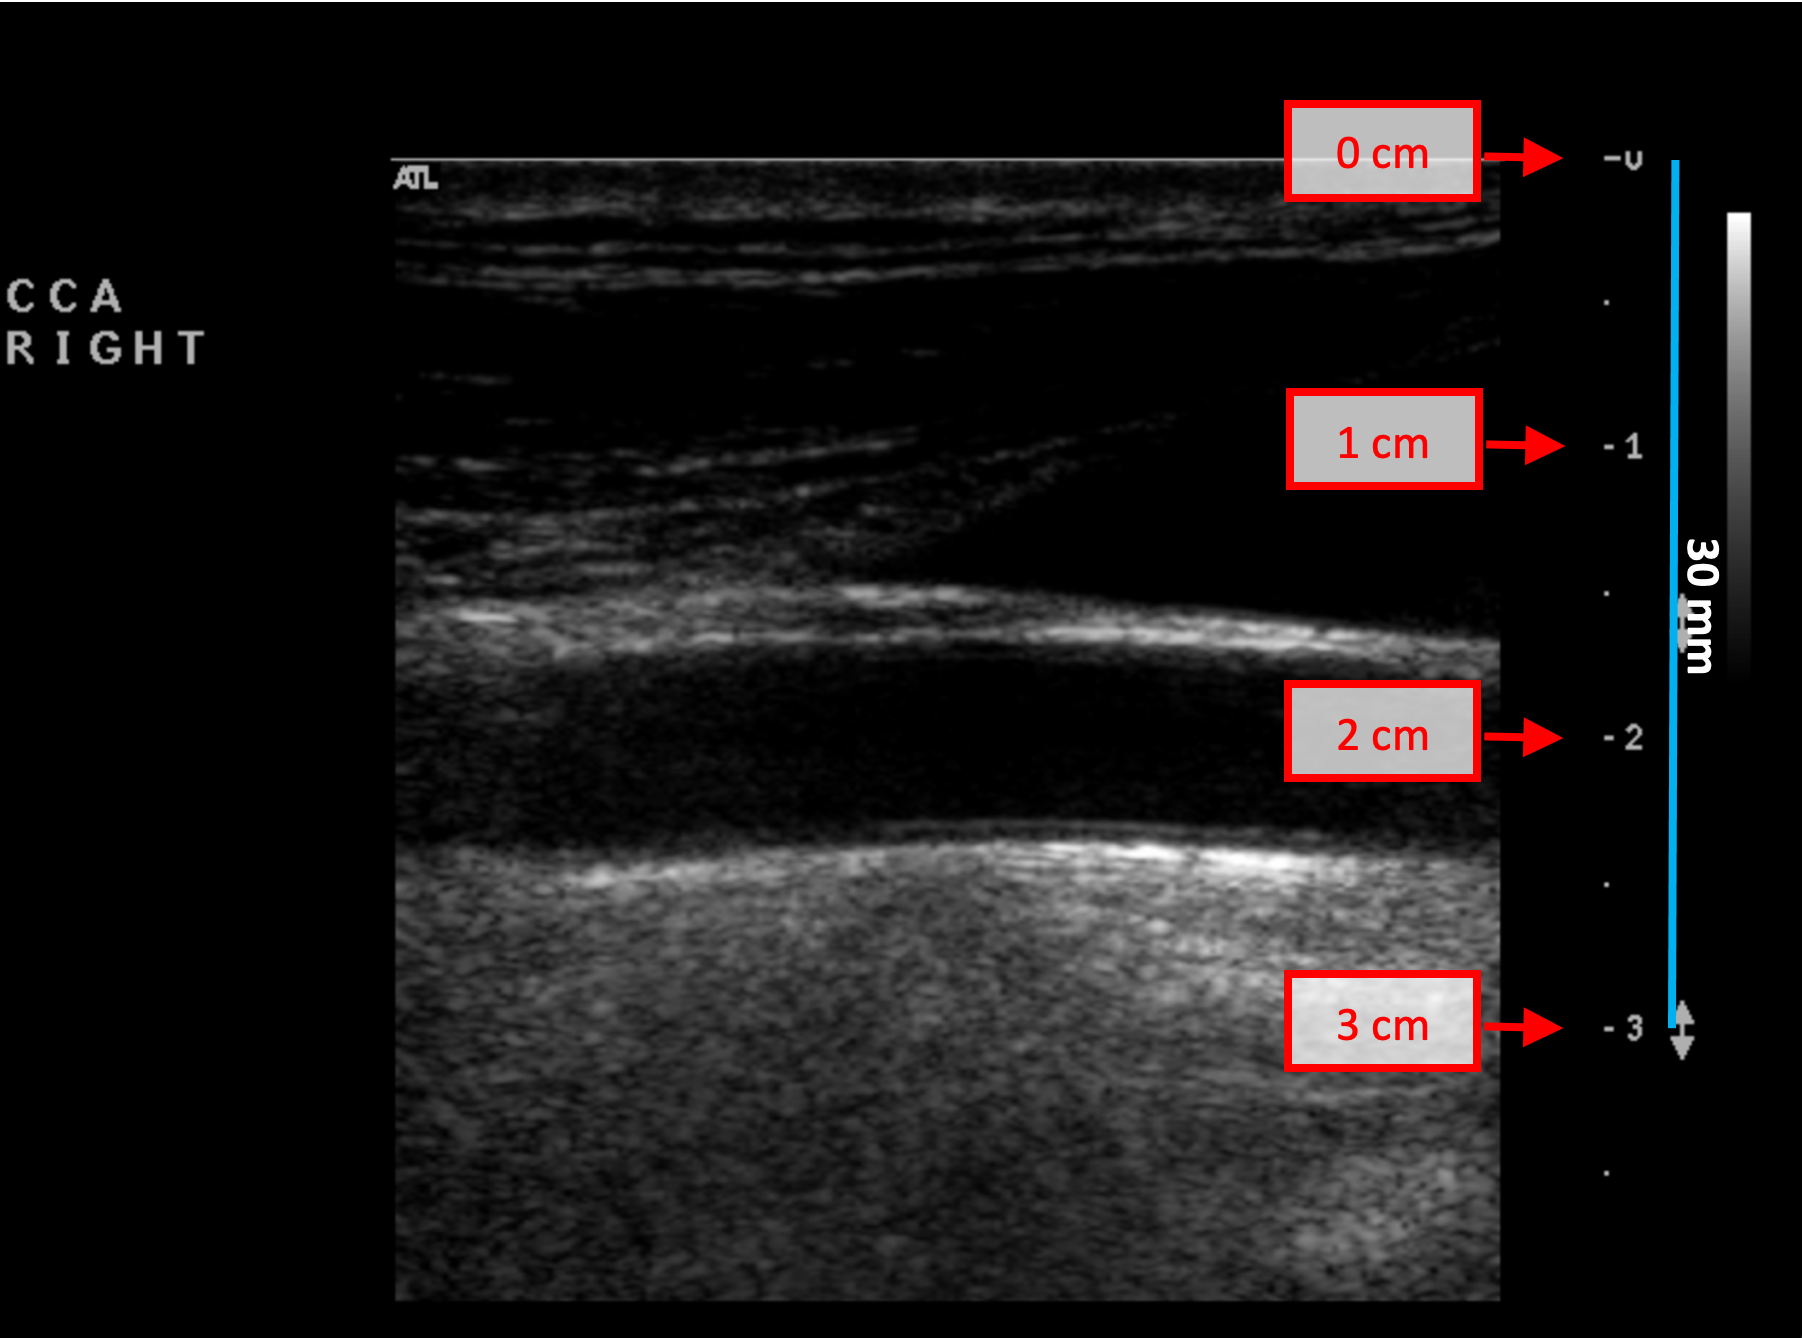

Exemples d'étalonnage en mode B

Les images suivantes présentent des exemples d'étalonnage de l'image en mode B. Les éléments graphiques en rouge indiquent où trouver les informations relatives à la profondeur de l'image échographique.